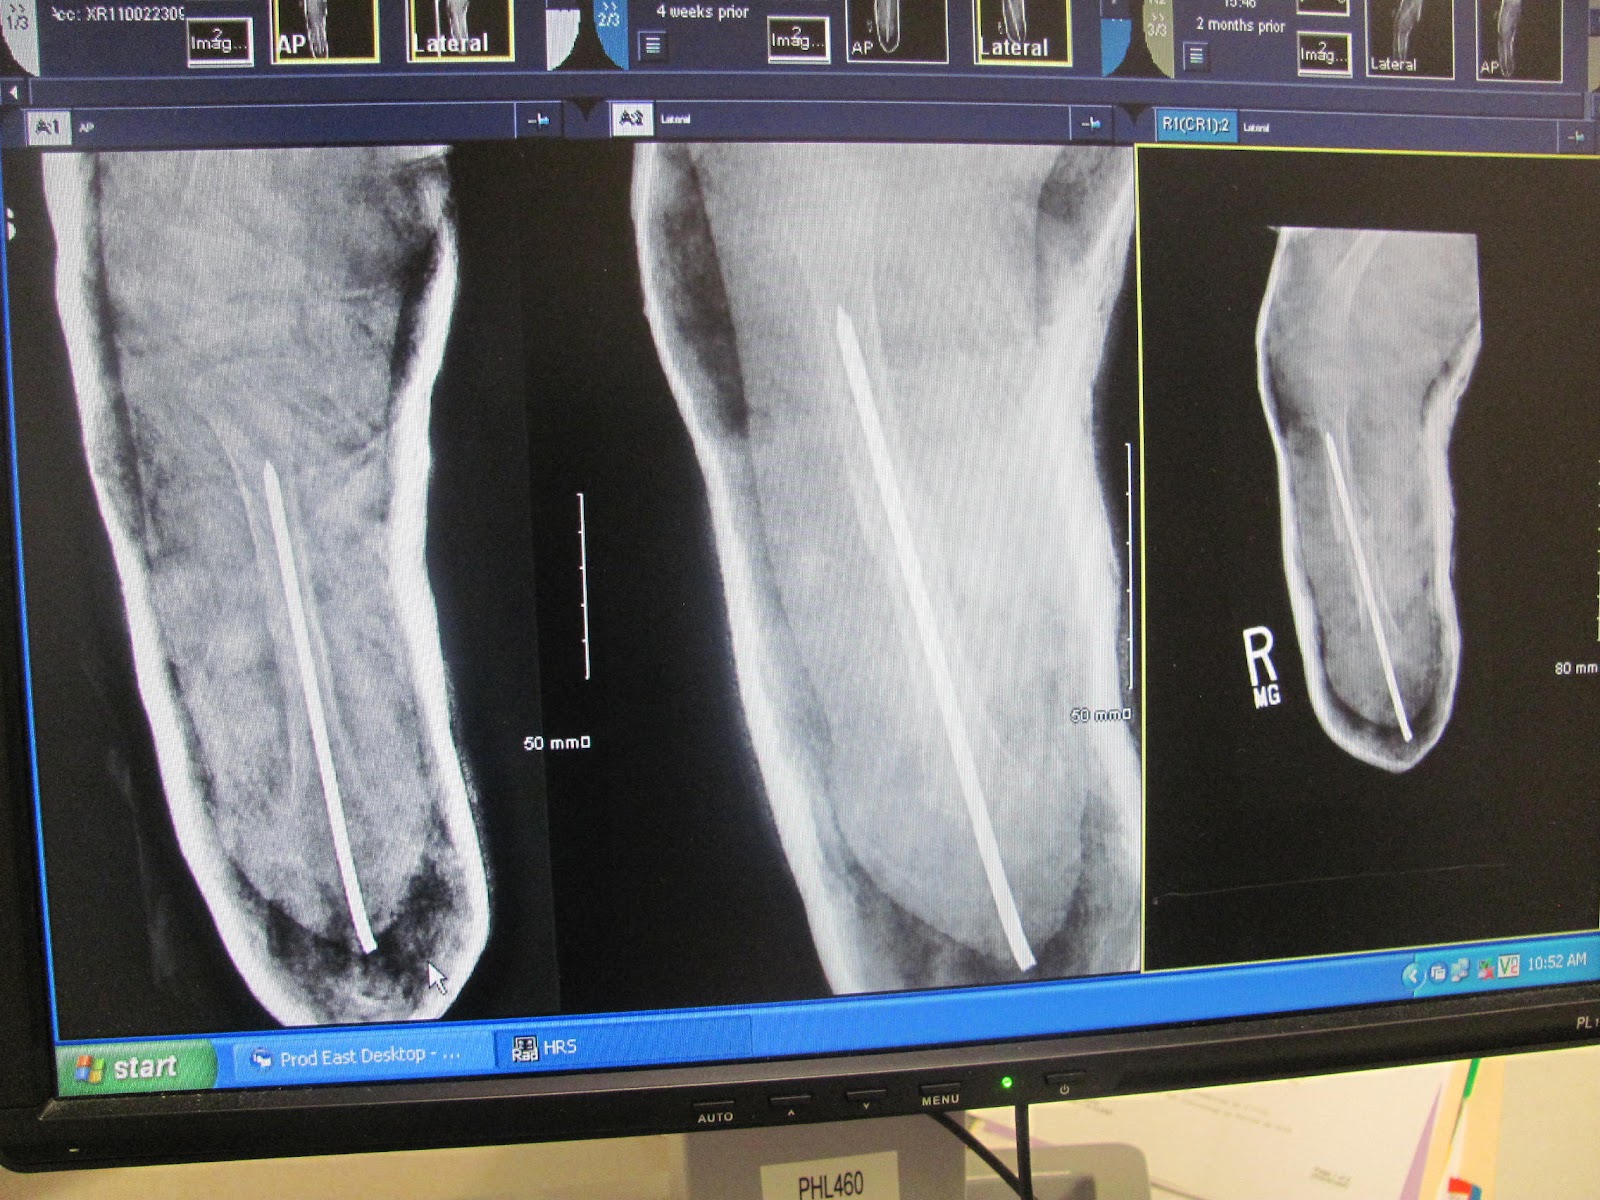

Laura had a series of X-rays to show how her tibia and heel were healing. The day the rod came out was not very pleasant for her. : (